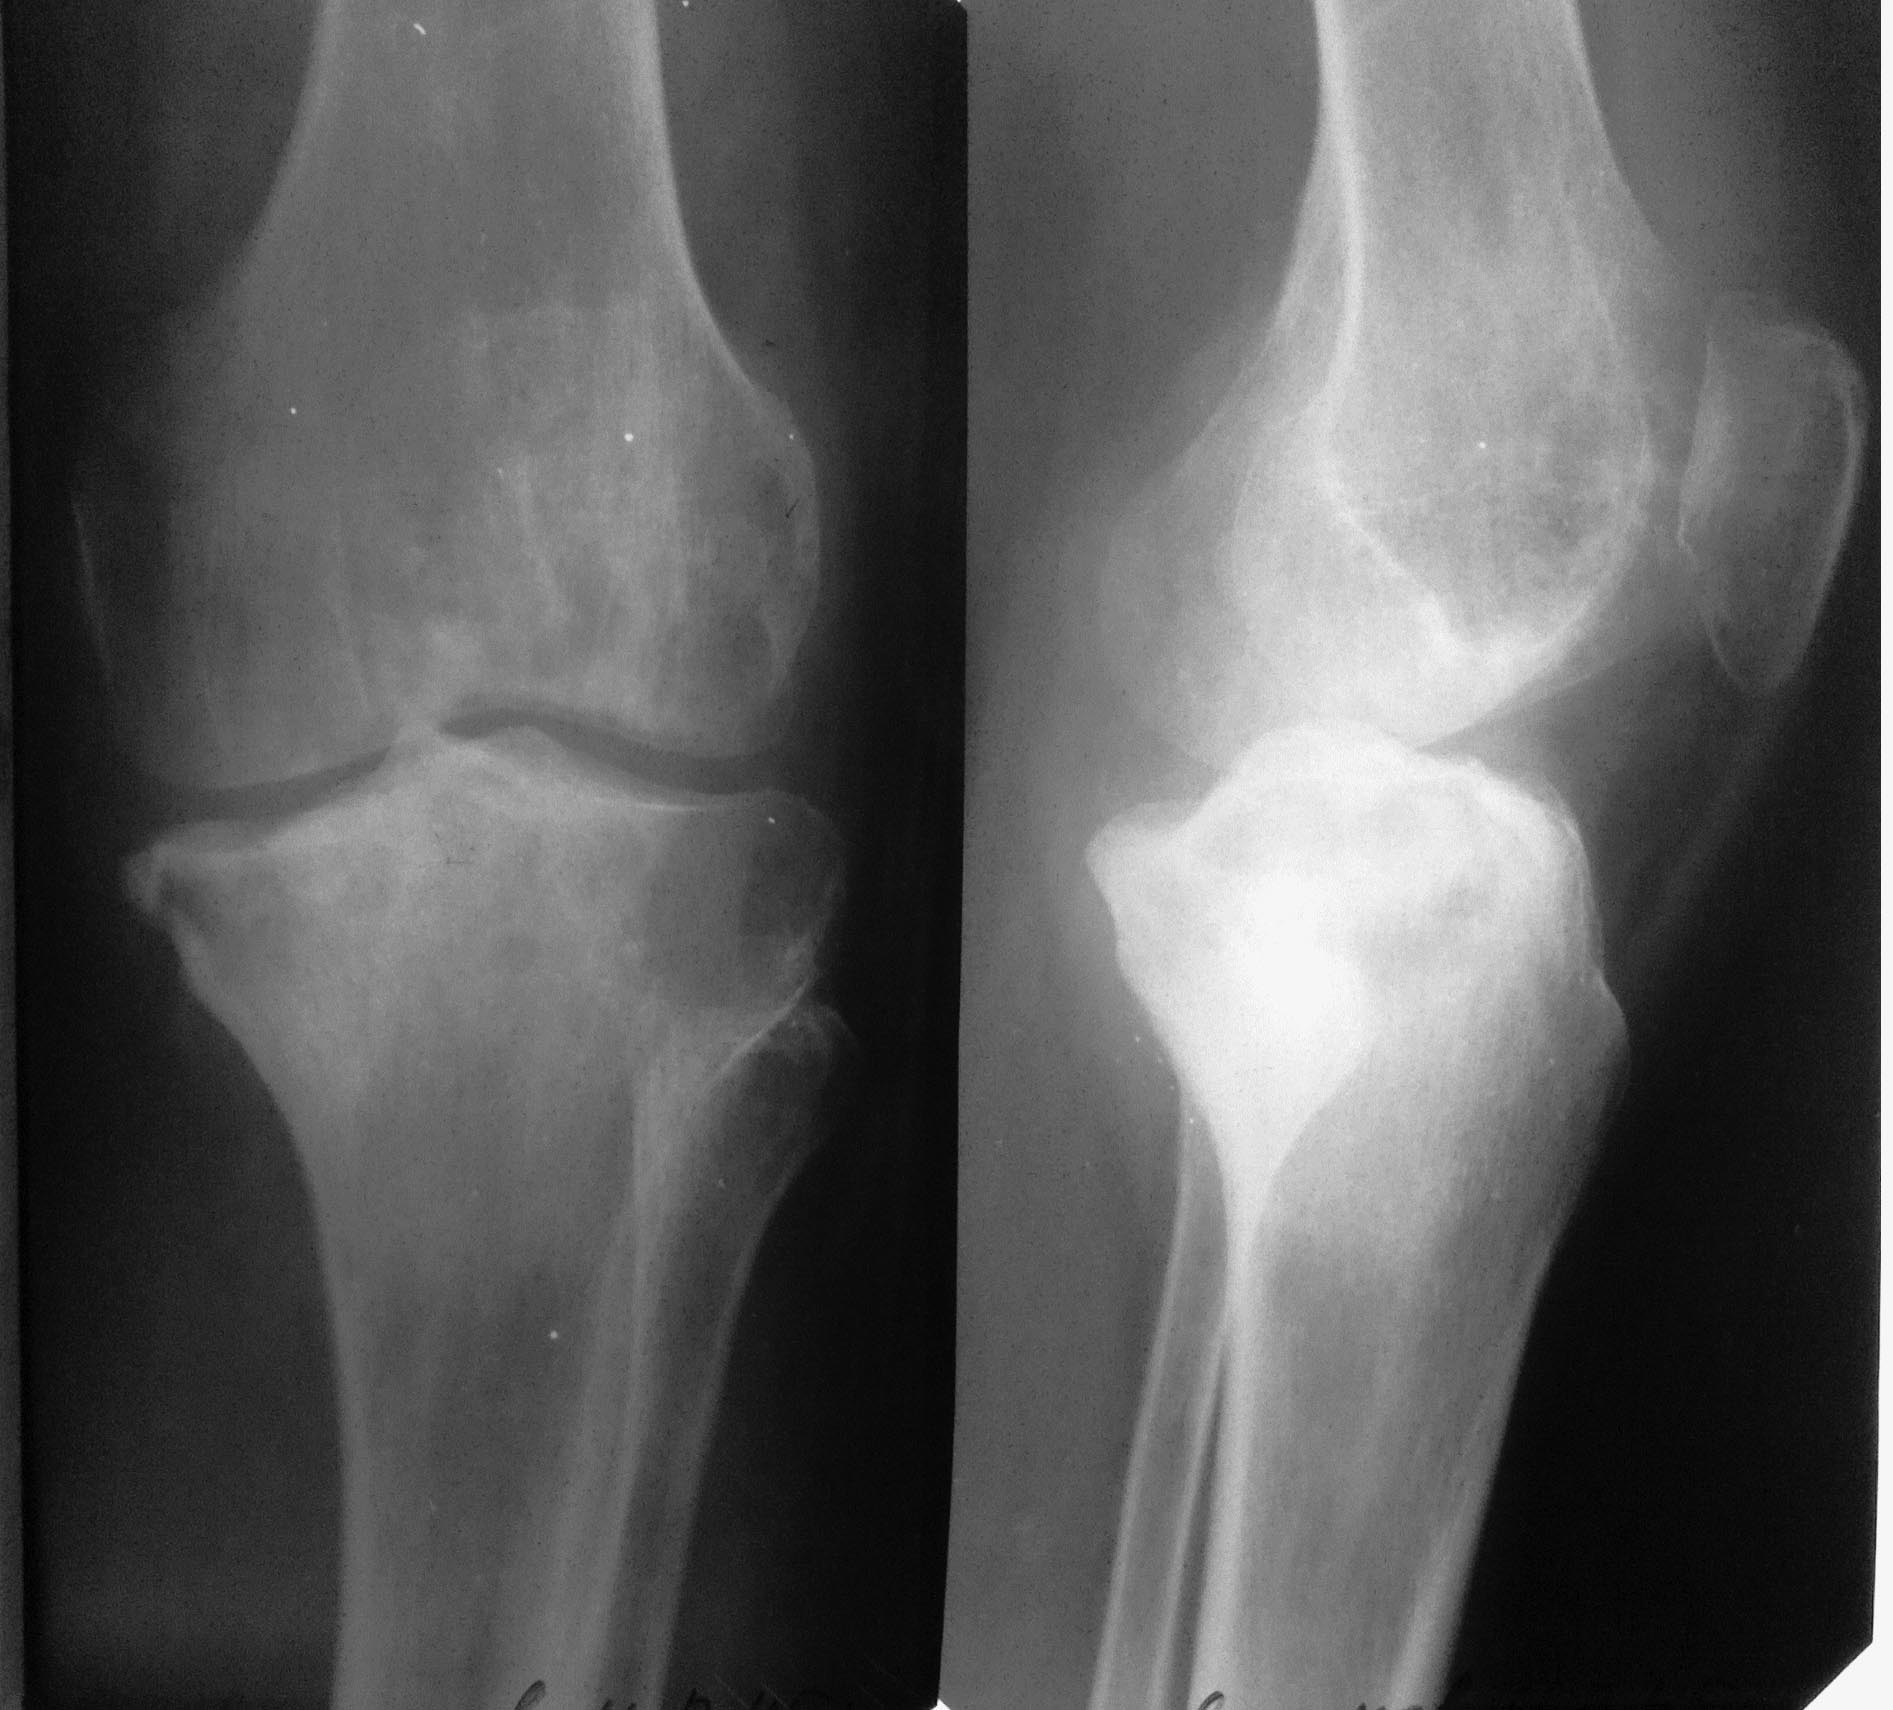

Мужчина 46 лет, электрик РЖД. Болен год. Боли в левом коленном суставе.

Ходит с тростью с апр 2012, конечность опорная, функция сустава сохранена, внешне сустав интактен, отека, гиперемии, жидкости в суставе - нет. Нормального телосложения и питания, активный. Амплитуда движений почти полная, болезненность при макс. сгибании.

РГ граммы - янв 2013